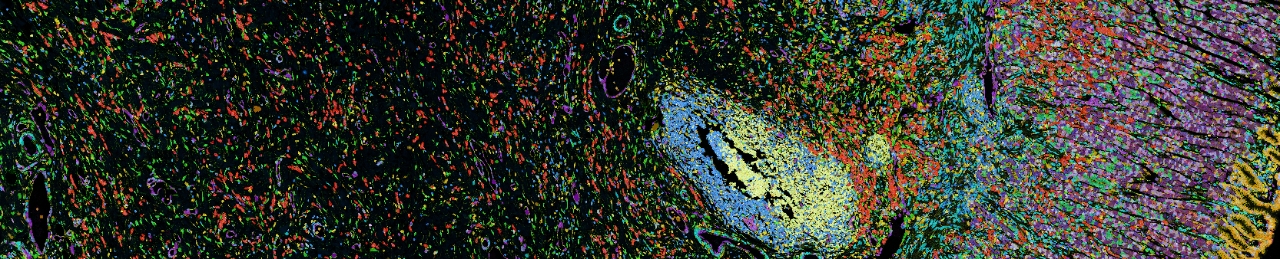

Recent advances in spatial multi-omics, molecular imaging, spatial functional genomics, 3D modeling and artificial intelligence (AI) now make it possible to decode the biological language of intercellular interactions. This reveals how cells are organized within tissues, how cell organization and interactions evolve during disease progression and therapy and how these changes influence clinical outcomes.

This video (with no sound) shows some of the center's work with 3D spatial architecture.